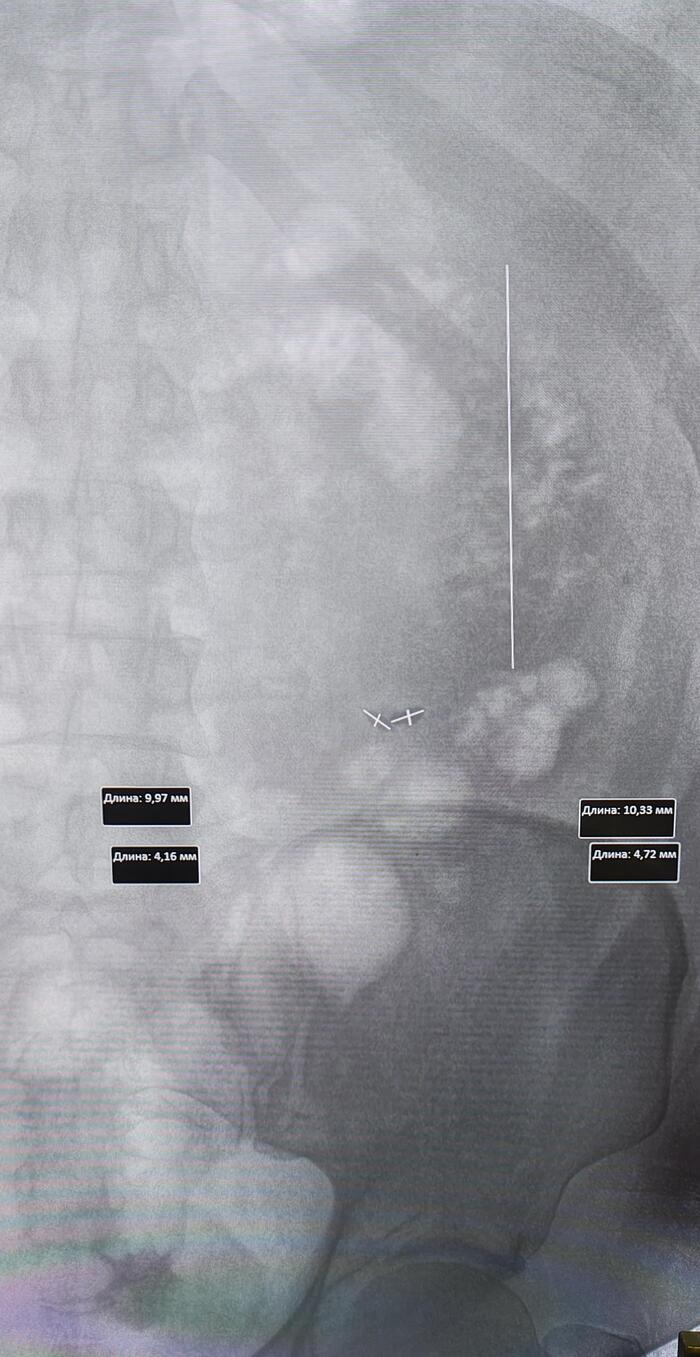

Описание: Правая почка размерами 52х53х140 мм. Корковое и мозговое вещество дифференцируются. Толщина паренхимы до 18 мм. В структуре - множественные кисты до 59*48 мм, с тонкими перегородками до 2 мм, без кальцинатов.Чашечно-лоханочная система почки не расширена, размер лоханки на выходе из почки – 4 мм. Паранефральная клетчатка не изменена.Ворота почки ориентированы в соответствии с нормой. Отхождение почечной артерии от брюшной аорты обычное.Мочеточник – не расширен – до 2 мм в диаметре.Левая почка размерами 49х52х99 мм. Корковое и мозговое вещество дифференцируются. Толщина паренхимы до 17 мм. В структуре - множественные кисты до 61*49 мм, с тонкими перегородками до 2 мм, без кальцинатов.Чашечно-лоханочная система почки не расширена, размер лоханки на выходе из почки – 4 мм. Паранефральная клетчатка не изменена.

Заключение: Множественные кисты обеих почек (Bosniak I).